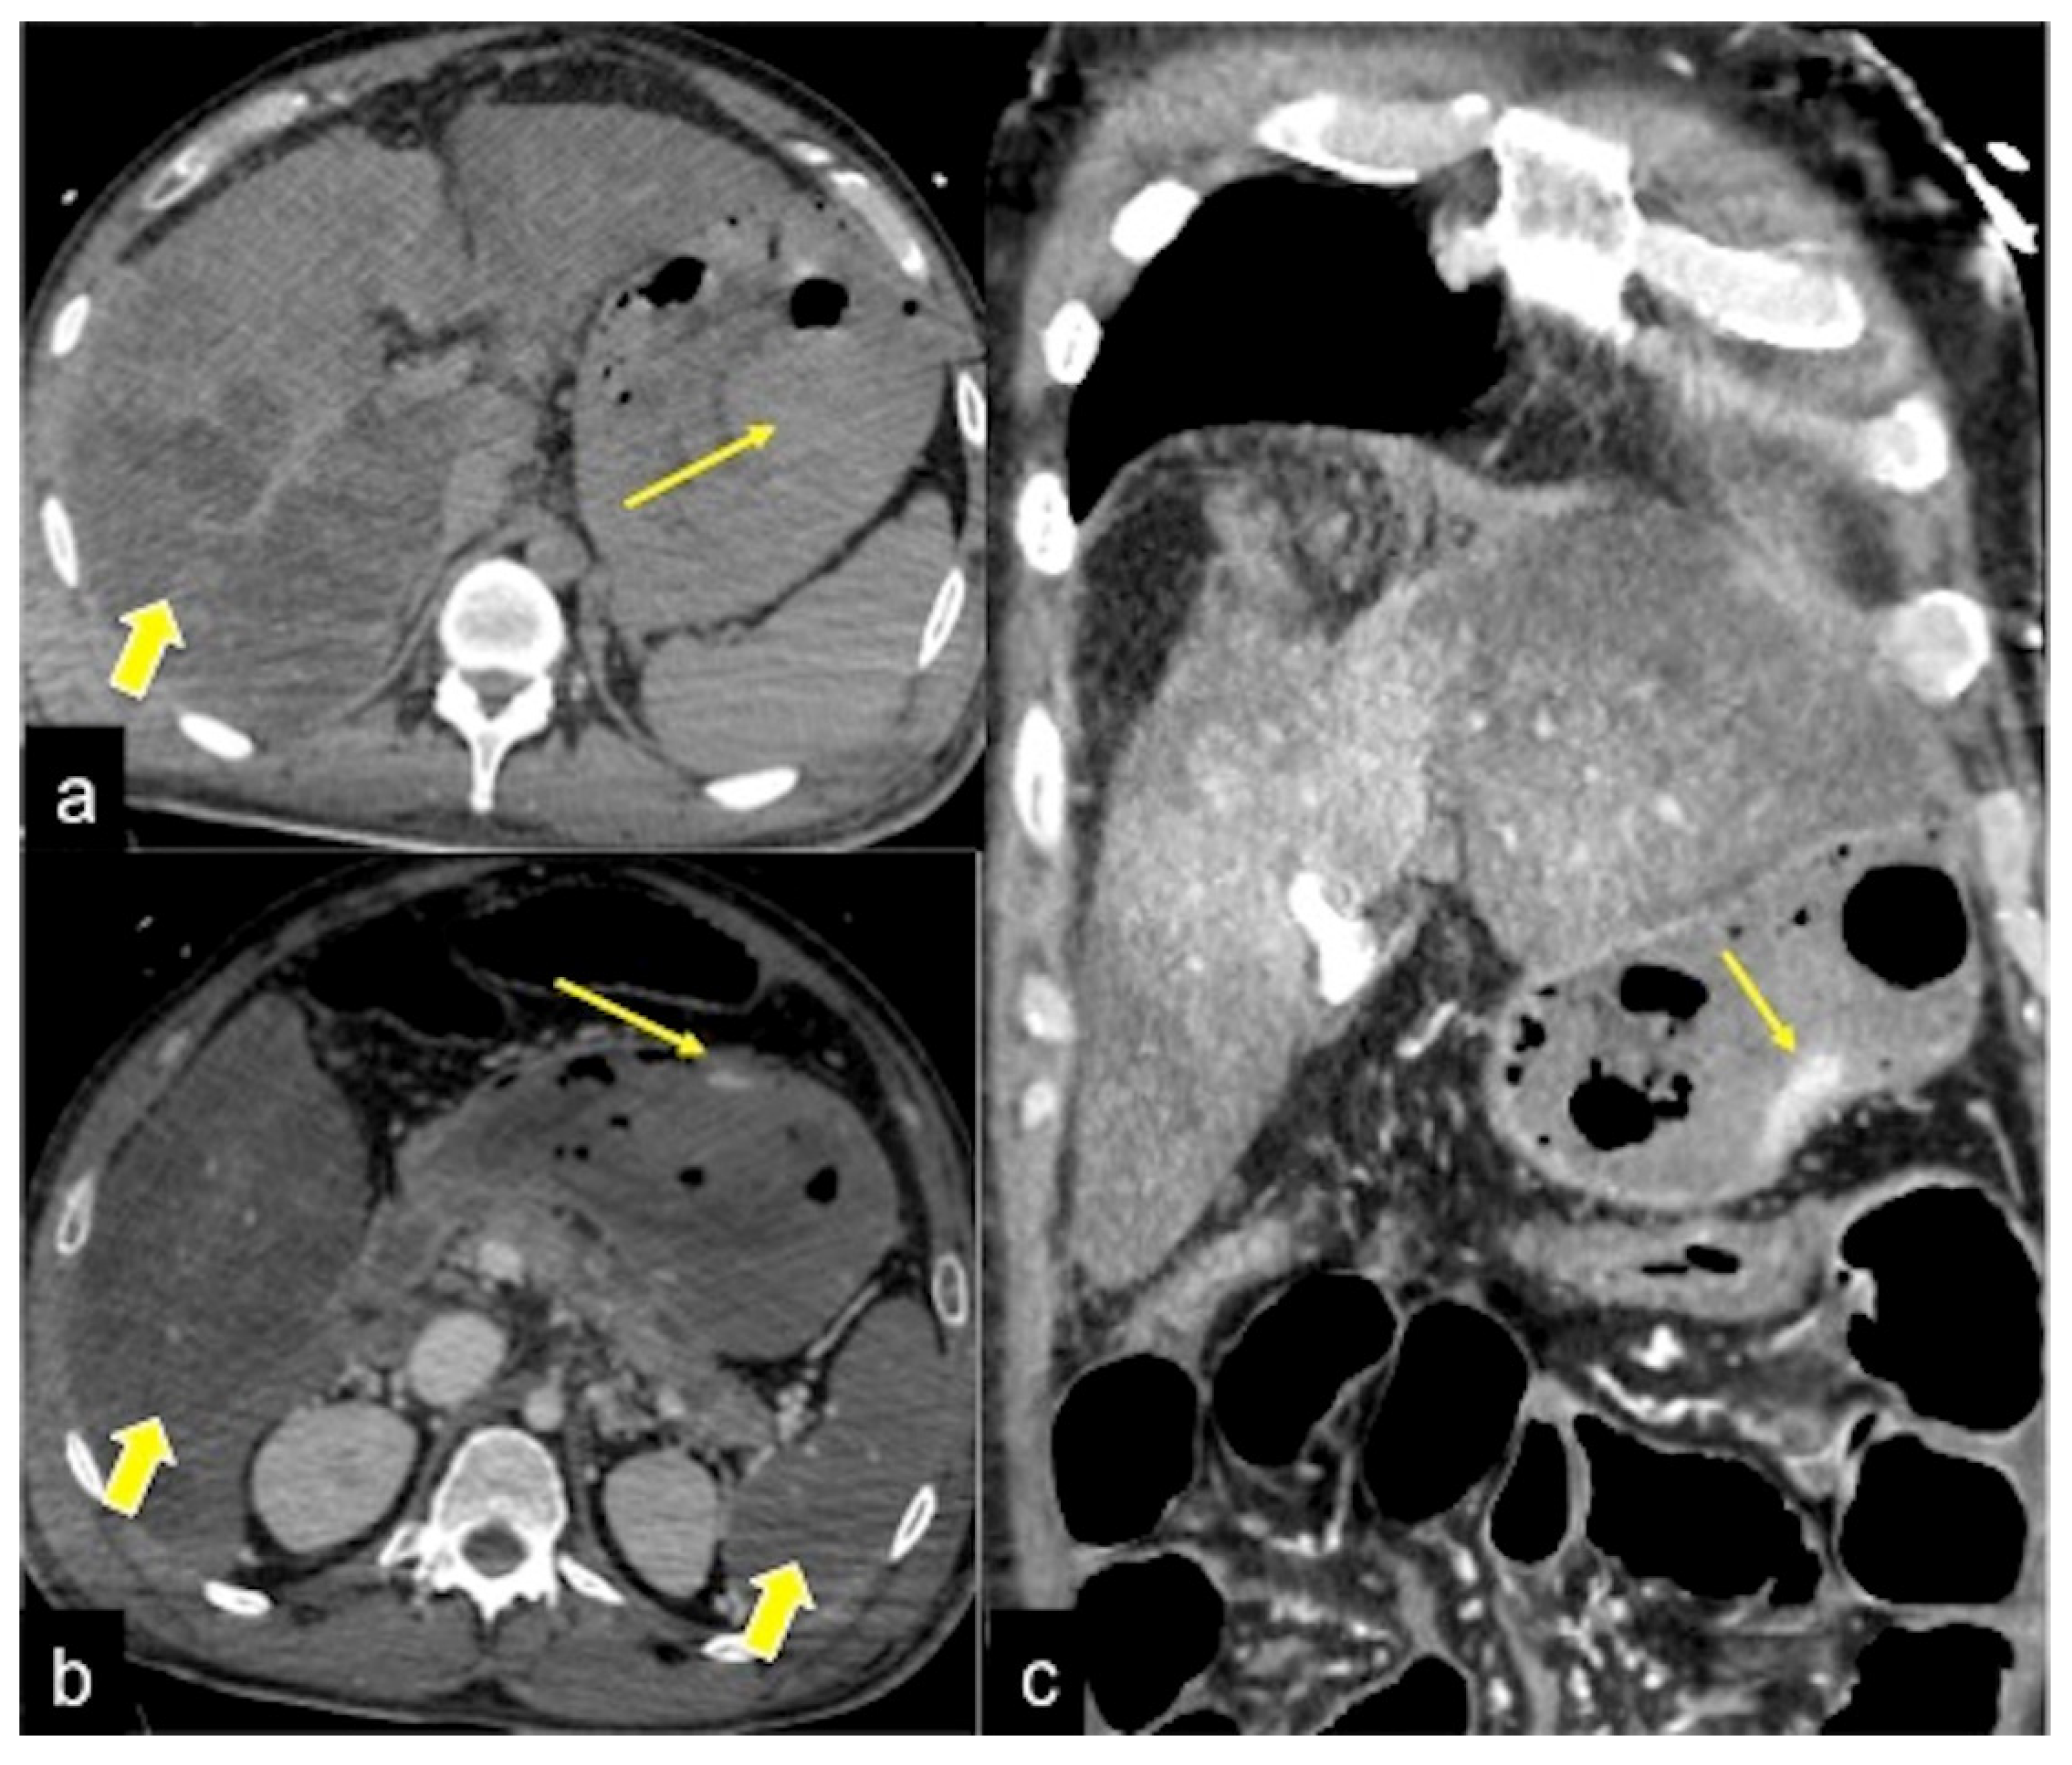

| Gastrointestinal Stromal Tumour (GIST) (Figure 26) | Asymptomatic or bleeding. | Soft tissue density mass with variable areas of necrosis. They are usually highly vascularised and the enhancement of the lesion may vary from homogeneous to peripheral and irregular depending on the lesion dimension and grade of malignancy. |

| GIST | Asymptomatic or bleeding. | Soft tissue density mass with variable areas of necrosis. They are usually highly vascularised and the enhancement of the lesion may vary from homogeneous to peripheral and irregular depending on the lesion dimension and grade of malignancy. |